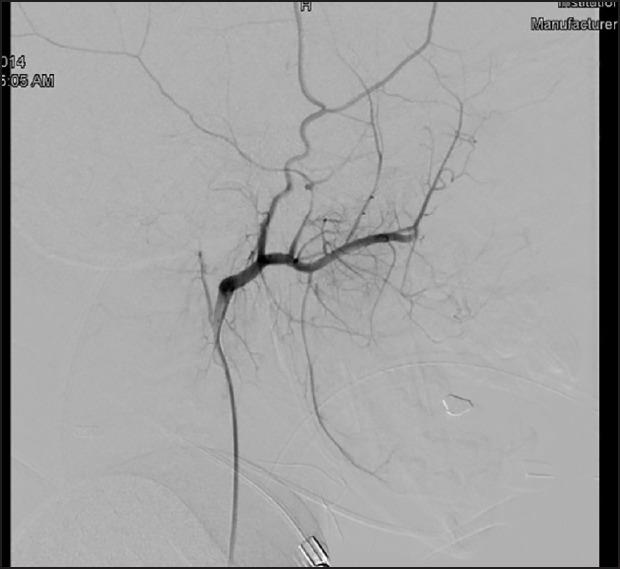

Juvenile psammomatoid ossifying fibroma (JPOF) is a rare, slowly progressive tumor of the extragnathic craniofacial bones, with a tendency toward locally aggressive behavior and recurrence. The pathognomonic histopathologic feature is the presence of spherical ossicles, which are similar to psammoma bodies. Very few cases in association with secondary aneurysmal bone cyst (ABC) formation have been reported in literature. Treatment consists of complete surgical removal. However, incomplete excision has been associated with a high local recurrence rate. The prognosis is good because malignant change and metastasis have not been reported. The authors are reporting a case of JPOF of the ethmoid bones with secondary ABC in a 7-year-old female patient.

青少年砂粒样骨化性纤维瘤(JPOF)是一种罕见的、生长缓慢的颌外颅面骨肿瘤,具有局部侵袭性行为和复发倾向。其特征性组织病理学表现是存在球形小骨片,类似于砂粒体。文献中报道的与继发性动脉瘤样骨囊肿(ABC)形成相关的病例极少。治疗方法为手术彻底切除。然而,切除不完整与高局部复发率相关。由于尚未报道有恶变和转移情况,其预后良好。作者报道了一例7岁女性患者筛骨JPOF伴继发性ABC的病例。